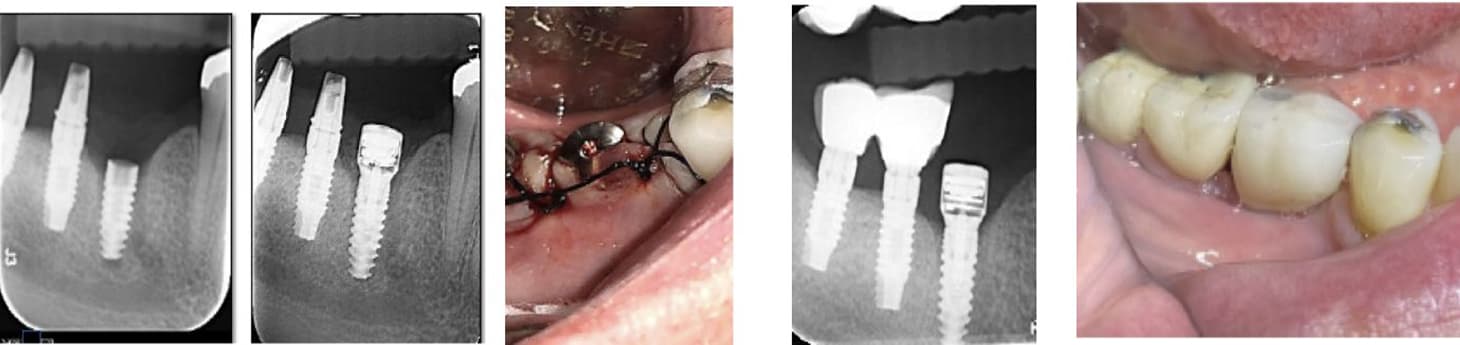

A 70-year-old healthy patient presented with inflammatory environment and advanced vertical bone loss around two adjacent implants supporting a fixed bridge. The treatment protocol included removal of the prosthetic bridge, thorough non-surgical debridement and deep curettage of the affected sites, followed by the application of MED healing abutments to promote bone regeneration and reduce inflammation through localized electromagnetic stimulation.

Within three months, radiographic evaluation revealed substantial vertical bone regeneration, effectively restoring nearly the entire height of the previously resorbed bone. Bone levels improved from 2.5 mm and 2.3 mm of loss at baseline to 1.2 mm and 2.0 mm of residual pockets, representing approximately 100% recovery of the lost bone height. The regenerated bone exhibited dense, well-integrated structure, and the peri-implant tissue remained healthy with no recurrent inflammation.

• This case demonstrates the regenerative capability of MED healing abutments in reversing peri-implant bone loss and achieving implant preservation through a predictable, minimally invasive, and non-surgical approach.